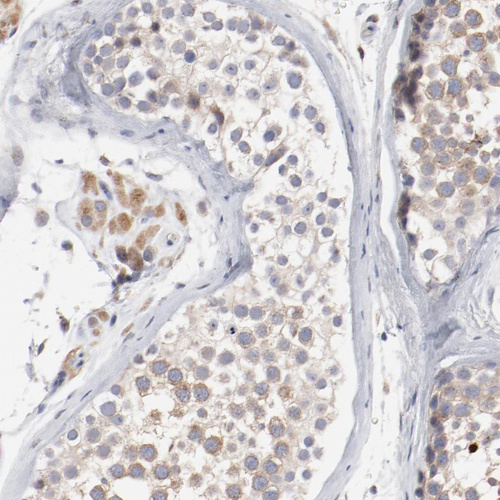

Immunohistochemistry analysis in human fallopian tube and lymph node tissues using HPA003543 antibody. Corresponding AK7 RNA-seq data are presented for the same tissues.